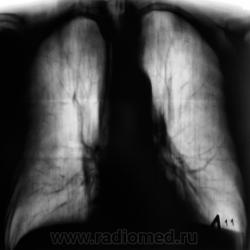

В последнее время пациент затежелел и был госпитализирован в областное ЛПУ, где было проведено несколько исследований.

1. Исследовавние.

2 Исследование.

С учетом срезы 11 см (снижение прозрачности легочной  ткани в медиальных отделах верхушечных сегментов), нами динамика была оценена, как "отрицательная.